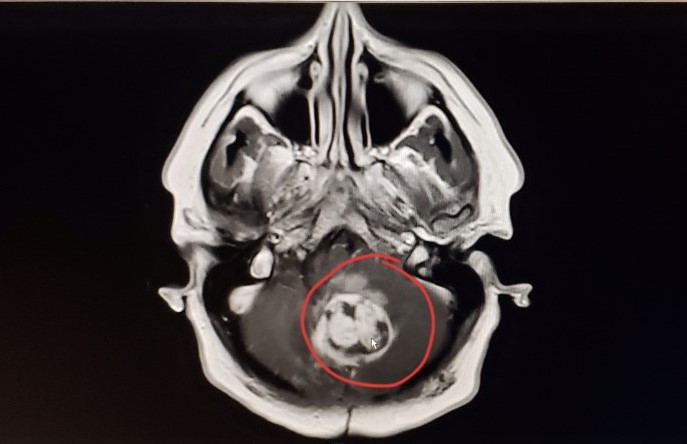

She was scheduled for a third craniotomy only nine months later in November 1998. “I was on the six-month routine of having MRIs. And so, they found it on this, and that it was growing.” She experienced cerebrospinal fluid (CSF) leaking out of her incision area. Sarah had to remain lying down until the incision dried out and closed.

On March 5th, 2020, Sarah’s world turned upside down for the fourth time; her tumour had come back. She was a 45-year-old businesswoman and fiancée to Todd. The following day she was put on a steroid treatment which increased her appetite and swelling throughout her body. She spent two months recovering in hospital during the pandemic.

On June 26th, 2020, Sarah Blanchard went in for her fourth craniotomy. After being discharged from hospital in July, she was readmitted a week later. At that time a VP shunt was surgically placed in her brain at the back of her head.

The surgery was a success, however Sarah unfortunately developed radiation necrosis. This meant that the debris from her previous radiation treatment over 20 years ago had not completely dissipated inside her skull. The radiation necrosis caused a bacterial infection and pulmonary embolism. She experienced other complications of the condition, such as nausea, loss of appetite and low levels of potassium and iron. She was constantly subject to medication, tests, and procedures, including two lumbar punctures and a pic line.